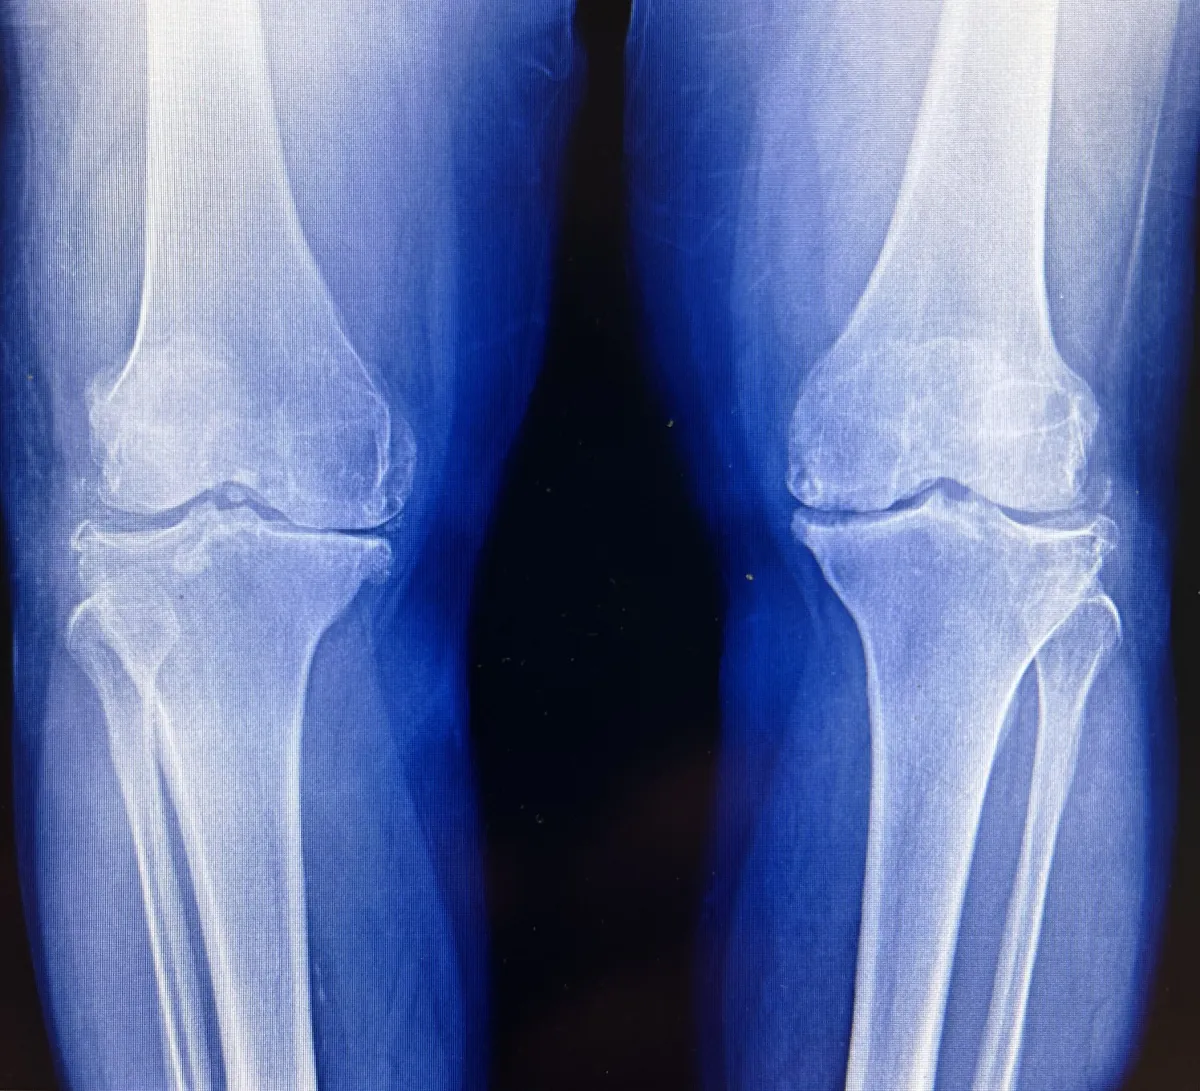

Knee Osteoarthritis (OA) NP2025, CC BY-SA 4.0, via Wikimedia Commons